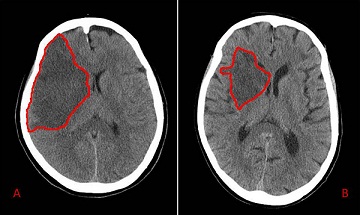

(»¡°£¼± ¾ÈÀÇ ºÎºÐÀÌ, ÇãÇ÷(Ischemia)ÀÌ ¿Í¼ ¼¼Æ÷±«»ç°¡ ÀÏ¾î³ ºÎºÐ)

³úÁ¹Áß(Òàðïñé)... ÀϹÝÀû ¾çŰ¾î·Î´Â StrokeÀ̶óÄ«°í... °í»óÇÑ ¾çŰ¾î·Î´Â Focal Cerebral Ischemia..¶óį.